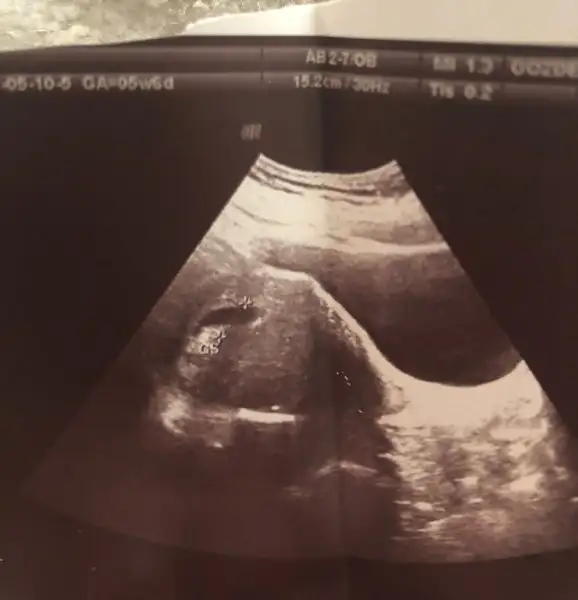

Benimkisi baya ince uzun bişey gibi canım. Tahlillerimi yapıp hafta başı doktora gidicem zaman geçmek bilmedi zaten. İnşallah gelişimi güzel devam ediyordur ve kalp atışını duyarız. Allah sana da bana da ve isteyen herkese de yavrularını kucağına almayı nasip etsin. Rica etsem kesenin ilk ultrason görüntüsünü atabilir misin

• B7ED2617-5E45-46D8-AB5E-6ACD2FB8ADCA.webp

B7ED2617-5E45-46D8-AB5E-6ACD2FB8ADCA.webp

6,7 KB · Görüntüleme: 482

Hemen hemen aynı benmkide böyleydi. Foto nasıl yükleniyor beceremedim :))

Eğer dosya büyük diyorsa fotoğrafın ekran görüntüsünü alıp Onu atabilirsin gerçekten de böyle mi ya :KK200:o kadar araştırdım bir tane buna benzeyen bulamadım ve hep kötü bilgiler bozulmul gebelik yüksek düşük tehlikesi vs.